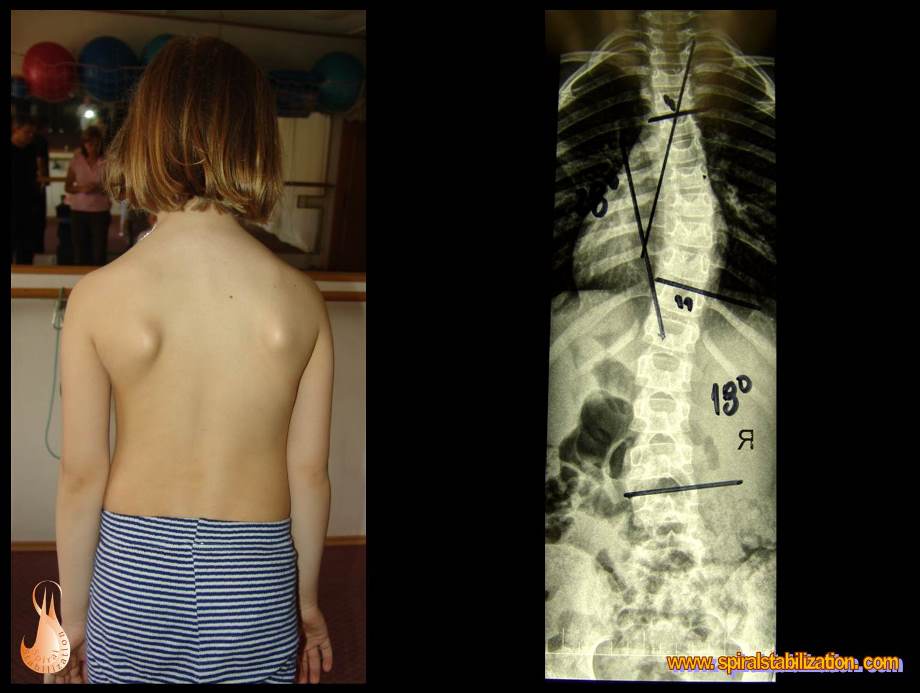

3 - Scoliosi

2 - Scoliosi fino ai 6 anni

Scoliosi fino ai 6 anni

B - 3 - 2